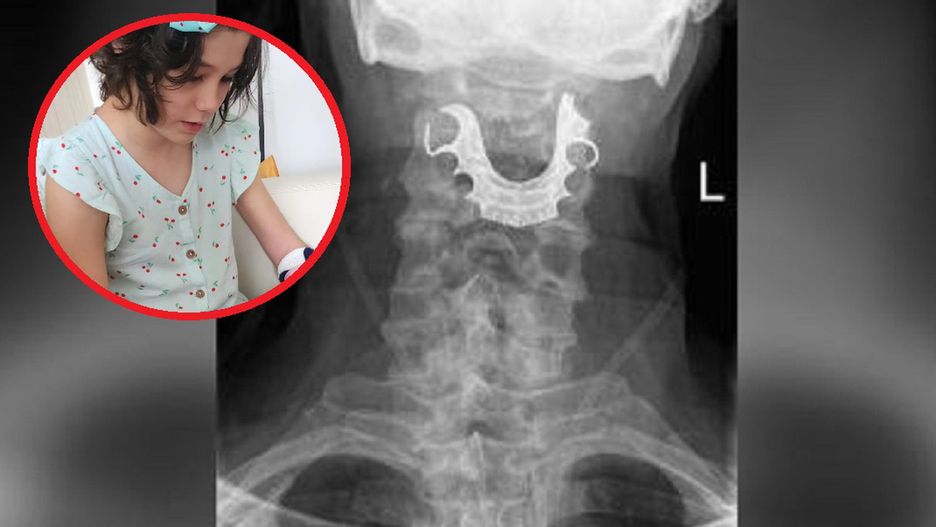

Gdy George Ivanoff z Florydy wbiegł do pokoju, skąd dobiegał krzyk jego córki, zobaczył, że 10-letnia Mila spadła z łóżka, na którym wcześniej skakała. Dziewczynka zraniła się w głowę i rękę, więc mężczyzna zawiózł ją na badania. Po wykonaniu prześwietlenia lekarze zauważyli w ciele dziecka coś nietypowego.

"Zrobili jej rentgen i zobaczyli obrzęk oraz zwapnienie, ale żaden z lekarzy nie miał pojęcia, co to jest. Powiedzieli nam, żebyśmy mieli na to oko i wrócili za dwa tygodnie. Wtedy zdaliśmy sobie sprawę, że coś jest nie tak" - opowiadał George w rozmowie z "The Sun".

Znajomy ortopeda w porozumieniu z innymi ekspertami dopiero po pół roku postawili diagnozę: kostniakomięsak. Ten rak kości atakuje zwykle chłopców i mężczyzn pomiędzy 12. a 24. rokiem życia i zwykle lokalizuje się w dłuższych kościach, szczególnie nóg i ramion. W przypadku Mili nowotwór był umiejscowiony w ręce w pobliżu nadgarstka.